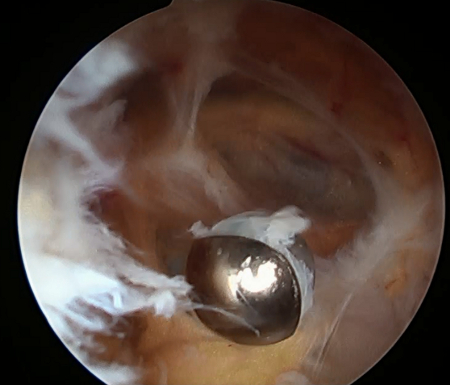

Arthroscopic resection of a popliteal cyst

From the collection of Dr John Kelly IV; used with permission

From the collection of Dr John D. Kelly IV; used with permission